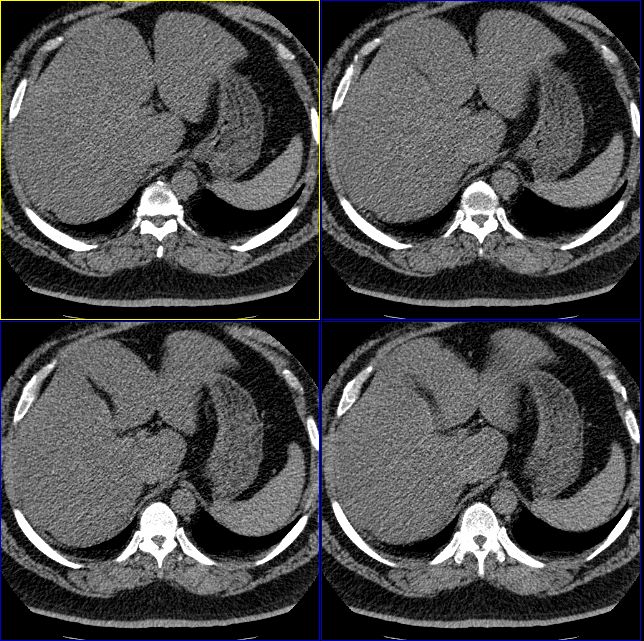

男性,37岁。体型极度肥胖,达300余斤。

支持脂肪肝,从图象看脾的密度要高于肝的

肝脏密度普遍减低,从图象看低于脾脏,支持脂肪肝。

肝脏密度普遍减低,从图象看低于脾脏,支持脂肪肝。必要时增强扫描